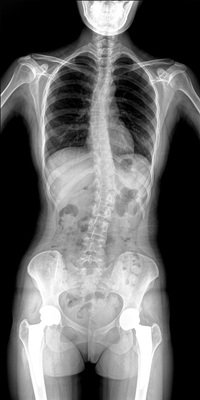

臨床需要對患者的脊柱情況有全面了解,故而術前術后均需要均需要借助DR拍攝X光片便于分析病情、明確診斷及術后觀察治療效果。大視野動態DR可以對患者的脊柱進行長尺寸攝影,一次拍攝就能獲取完整的脊柱全景圖像。診斷醫生通過拍攝后的影像測量全脊柱的生物角度、Cobb角等,為脊柱側彎的畸形矯正患者術前術后的檢查提供重要的診斷依據。

通過大視野動態DR進行全脊柱攝片,其得到的影像密度均勻、清晰、接緣處過渡自然。且操作更加便捷,不需要二次攝片然后進行圖像拼接,拍攝時間短,效率高。在減少輻射劑量的同時也能為臨床醫生帶來更精確的診斷信息。非拼接影像可保證雙腿測量(如力線)數據的準確性,有效避免攝影信息的丟失。給手術醫生提供準確的術前診斷數據,提高手術成功率。

綜上所述,大視野動態DR進行全脊柱成像能夠清晰的呈現骨關節結構,可以在全景脊柱圖像基礎上對角度值進行測量,能夠很好的反映骨骼的真實比例與長度,為臨床診斷和治療提供了更精確的數據,有著重要臨床應用價值。